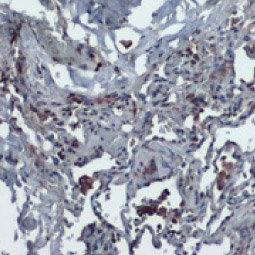

| Nucleocapsid (N) | Nucleocapsid (~419 a.a. in SARS-CoV-2) binds viral genomic RNA and forms a helical ribonucleocapsid. Involved in genome protection, viral RNA replication, virion assembly, and immune evasion. Interacts with M and nsp3 proteins. | 2 |